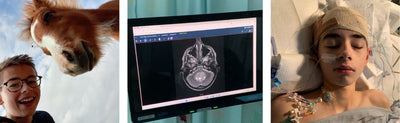

Sean Sweeney

5 min read